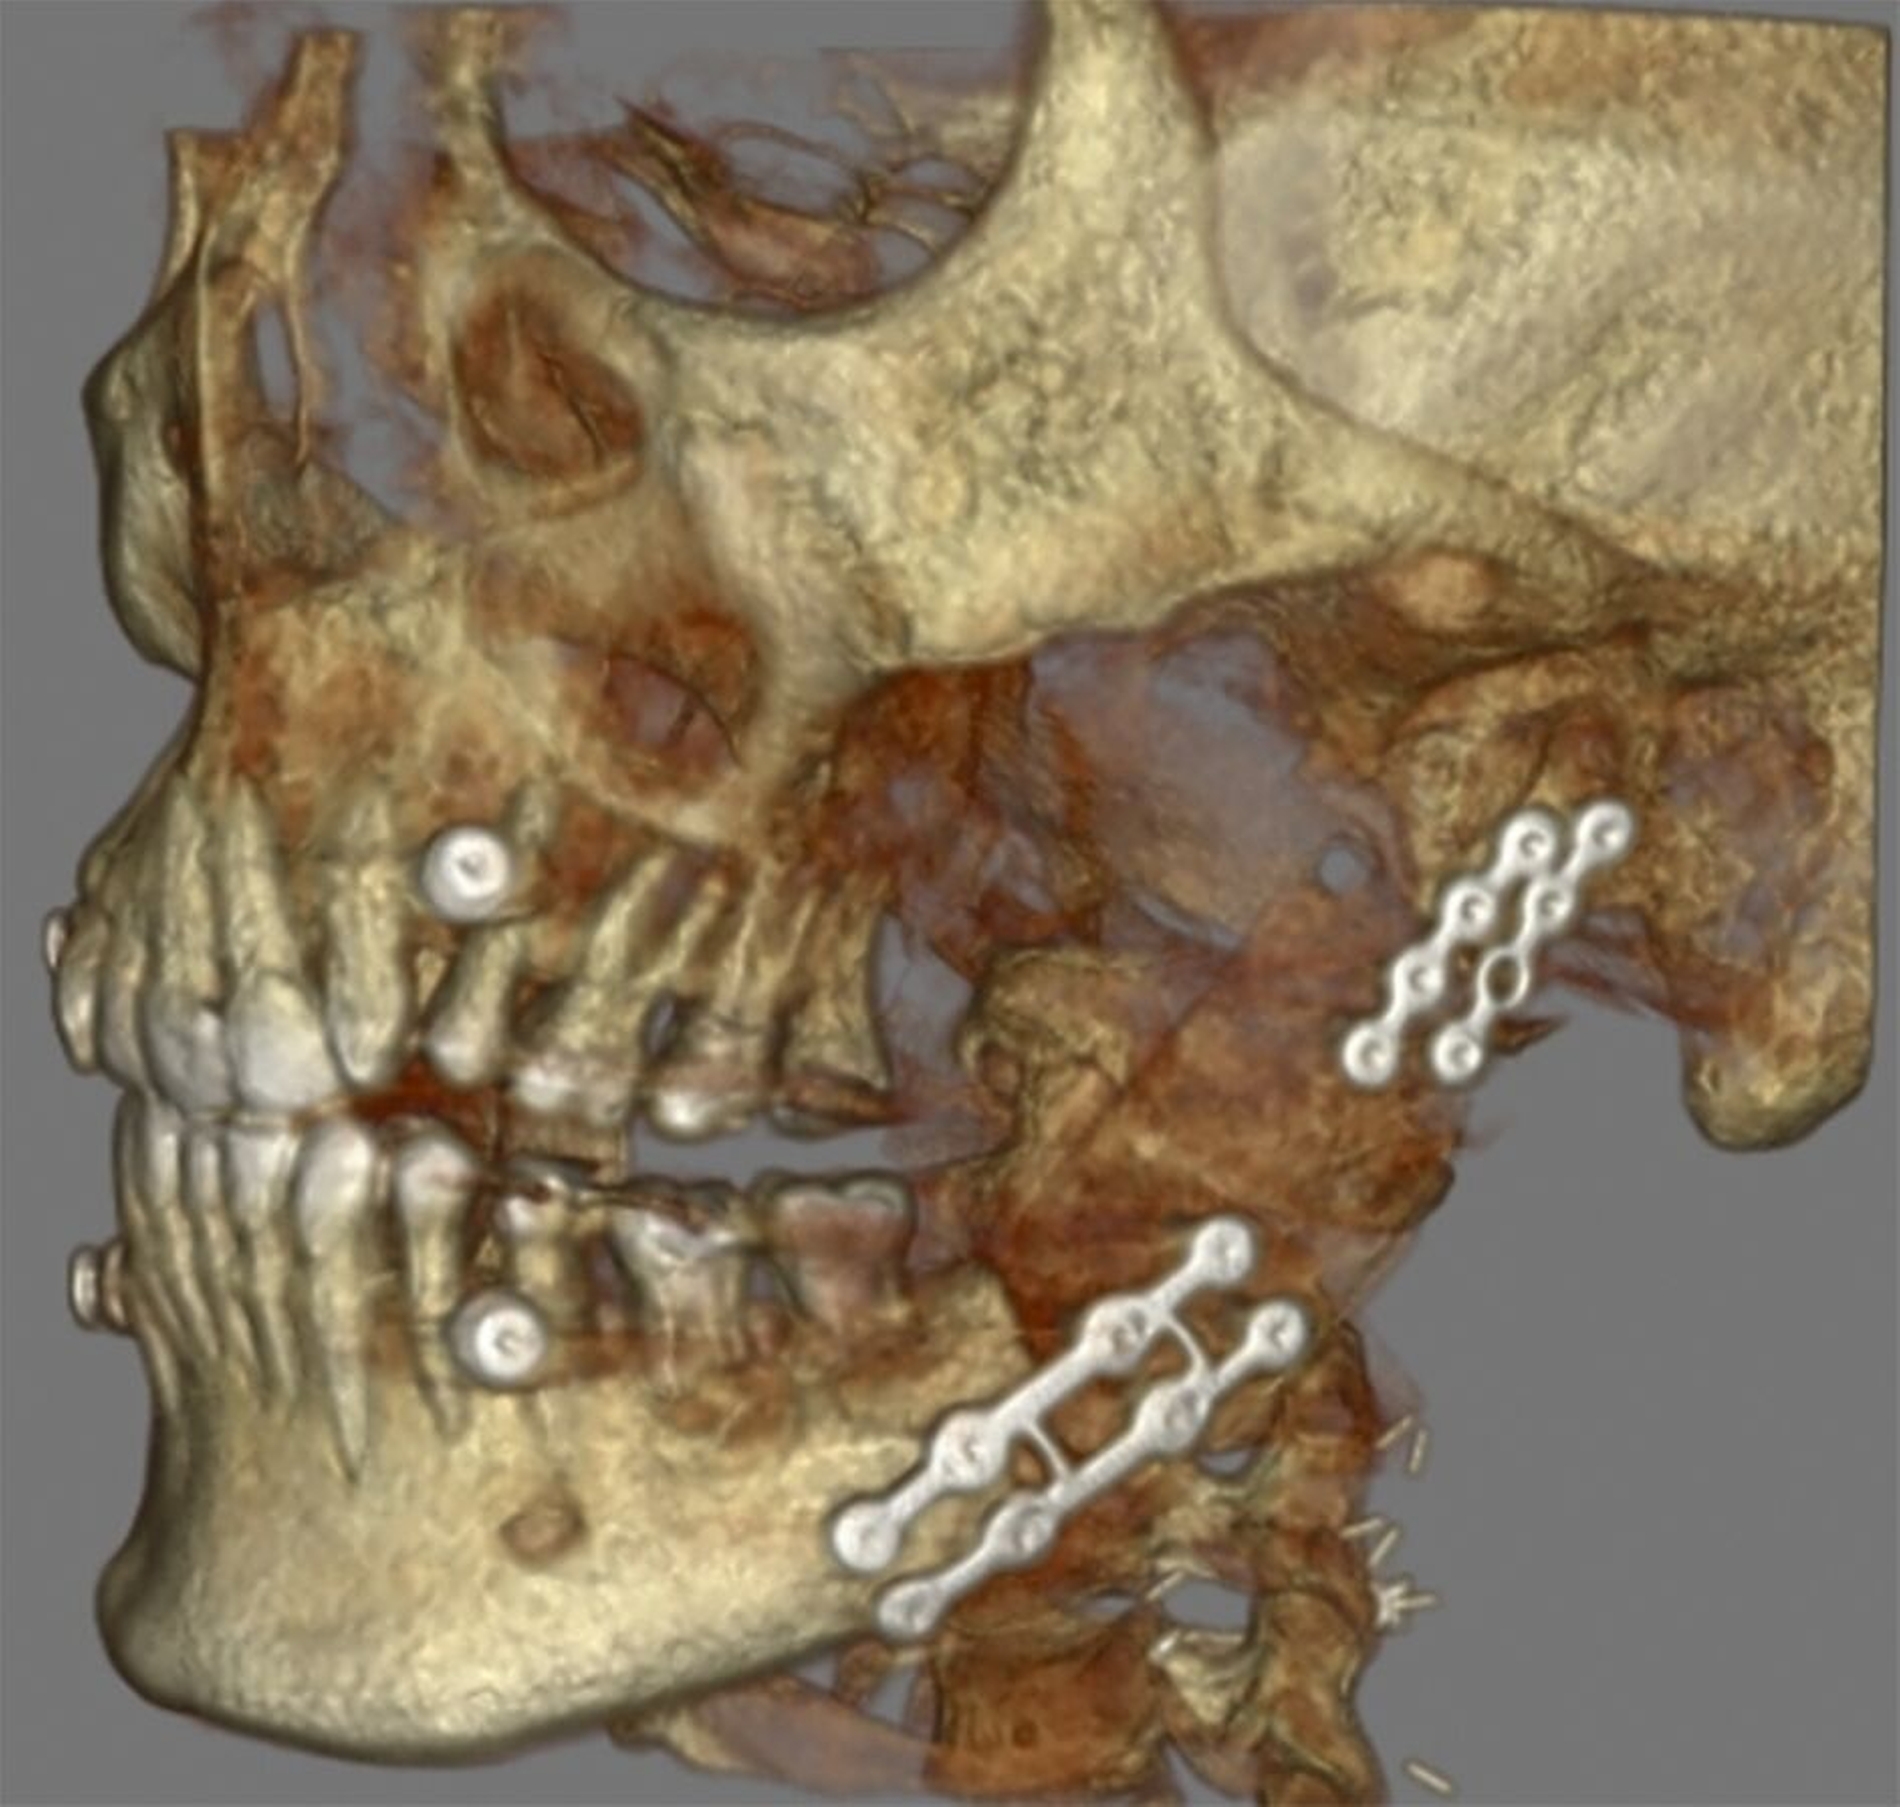

Aktuell befindet sich die Patientin im Rahmen der Tumornachsorge im engmaschigen klinischen Recall. Aufgrund der geringen Tumorgröße und nicht nachweisbarer lymphatischer Metastasierung konnte auf eine adjuvante Bestrahlung verzichtet werden. Die kürzlich erfolgte 12-Monats-CT-Kontrolle nach Therapie zeigte ein regelhaftes Ergebnis ohne Nachweis eines Lokalrezidivs oder pathologisch vergrößerter Lymphknoten (Abbildungen 4 und 5).